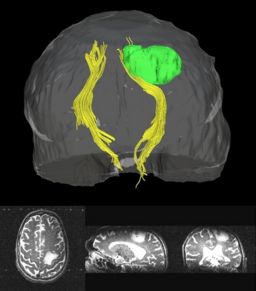

Clustered fibers in the region of the corticospinal tract have been used to identify regions of interest for slice-by-slice measurements of its diffusion properties in normals and tumor subjects. A pilot study (with Monica Lemmond at Harvard Medical School and Stephen Whalen and Alexandra Golby at Brigham and Women's Hospital/HMS) has demonstrated changes in tumor-affected tracts (relative to the contralateral side) beyond the apparent tumor border. A larger study is currently underway.

Atlas creation and automatic labeling has been performed in high-quality DTI datasets from Susumu Mori. Images showing example segmentation results are below. Work is underway to apply this atlas to segment additional datasets to define regions of interest that may be used in the study of schizophrenia.

Selected anatomical regions, automatically labeled using the cluster atlas in 3 subjects.